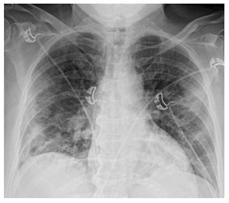

Стандартная РГ имеет низкую чувствительность в выявлении начальных изменений в первые дни заболевания и не может применяться для ранней диагностики. Информативность РГ повышается с увеличением длительности течения пневмонии. Рентгенография с использованием передвижных (палатных) аппаратов является основным методом лучевой диагностики патологии ОГК в отделениях реанимации и интенсивной терапии (ОРИТ). Применение передвижного (палатного) аппарата оправдано и для проведения обычных РГ исследований в рентгеновском кабинете. В стационарных условиях относительным преимуществом РГ в сравнении с КТ являются большая пропускная способность. Метод позволяет уверенно выявлять тяжелые формы пневмоний и отек легких различной природы, которые требуют госпитализации, в том числе направления в ОРИТ.

Вместе с тем, комплексная оценка анамнестических, клинических и рентгенологических данных позволяет определить клинически подтвержденный случай COVID-19, маршрутизировать пациента и начать противовирусную терапию.